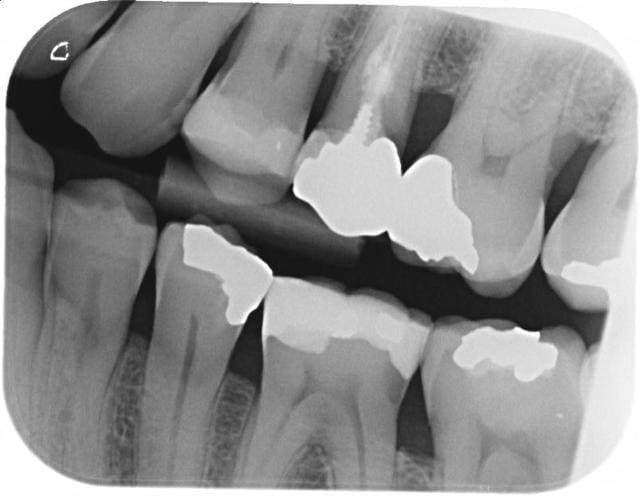

Je compare les btw precedents et tombe sur un hic au niveau de 36 en evolution depuis 2010.

Pour ce que je vois sur les radios, ces soins sont propres, mais pas exceptionnels. Notamment les faces proximales, reconstituées avec des matrices insuffisamment galbées qui produisent un point de contact presque occlusal et qui ne protège pas très bien l'espace inter dentaire en évitant aux aliments de se coincer.

Ceci étant, nous avons tous des patients qui ne passent pas assez les brossettes inter dentaires et déclenchent des caries cervicales incontrôlées.

A stade où nous en sommes, la pulpectomie semble difficile à éviter. Ton patron devrait s'en réjouir, sauf s'il n'est pas payé au pourcentage.

je m'inquiéterais aussi pour la 25.

face distal de 23 également, y a une petite radio clarté.

Je rescelle zirkon de 11h30 au multilink et radio de controle pour voir si j ai pas oublie du materiau en interproximal. Et bingo!!!

ps: la patiente etait a la clinique il y a 2 mois pour controle avec 4 btw.